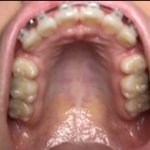

'발치공간'

발치공간

다닫혔는데 다시생기는경우있어????????...

[댓글부탁해] 교정

이정도 남았는데 이번년도안에

[댓글부탁해] 교정끝난애들아 나

몇달이면닫힐까?